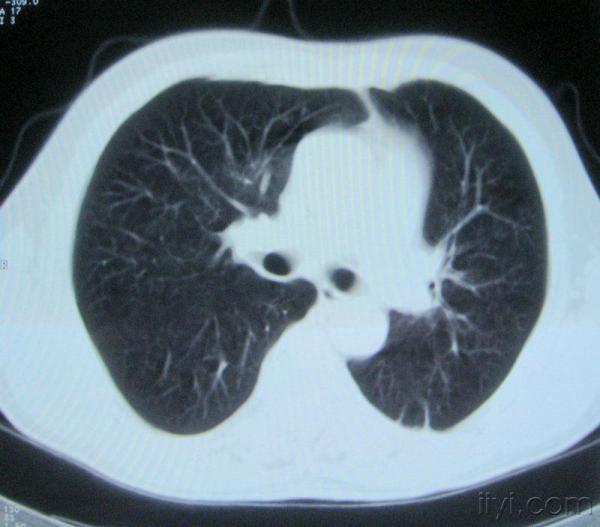

男。60岁,胸片示支气管炎治疗后复查CT。

你指那个肯定是淋巴结,中央系坏死,这很常见,特别在双侧腹股沟会经常看到。这个双侧腋窝及纵隔见多发小淋巴结征。

根据位置考虑应该是淋巴结,密度不均,是因为肿大的淋巴结中心液化坏死